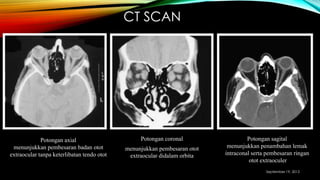

CT SCAN

Potongan axial

menunjukkan pembesaran badan otot

extraocular tanpa keterlibatan tendo otot

Potongan coronal

menunjukkan pembesaran otot

extraocular didalam orbita

Potongan sagital

menunjukkan penambahan lemak

intraconal serta pembesaran ringan

otot extraoculer